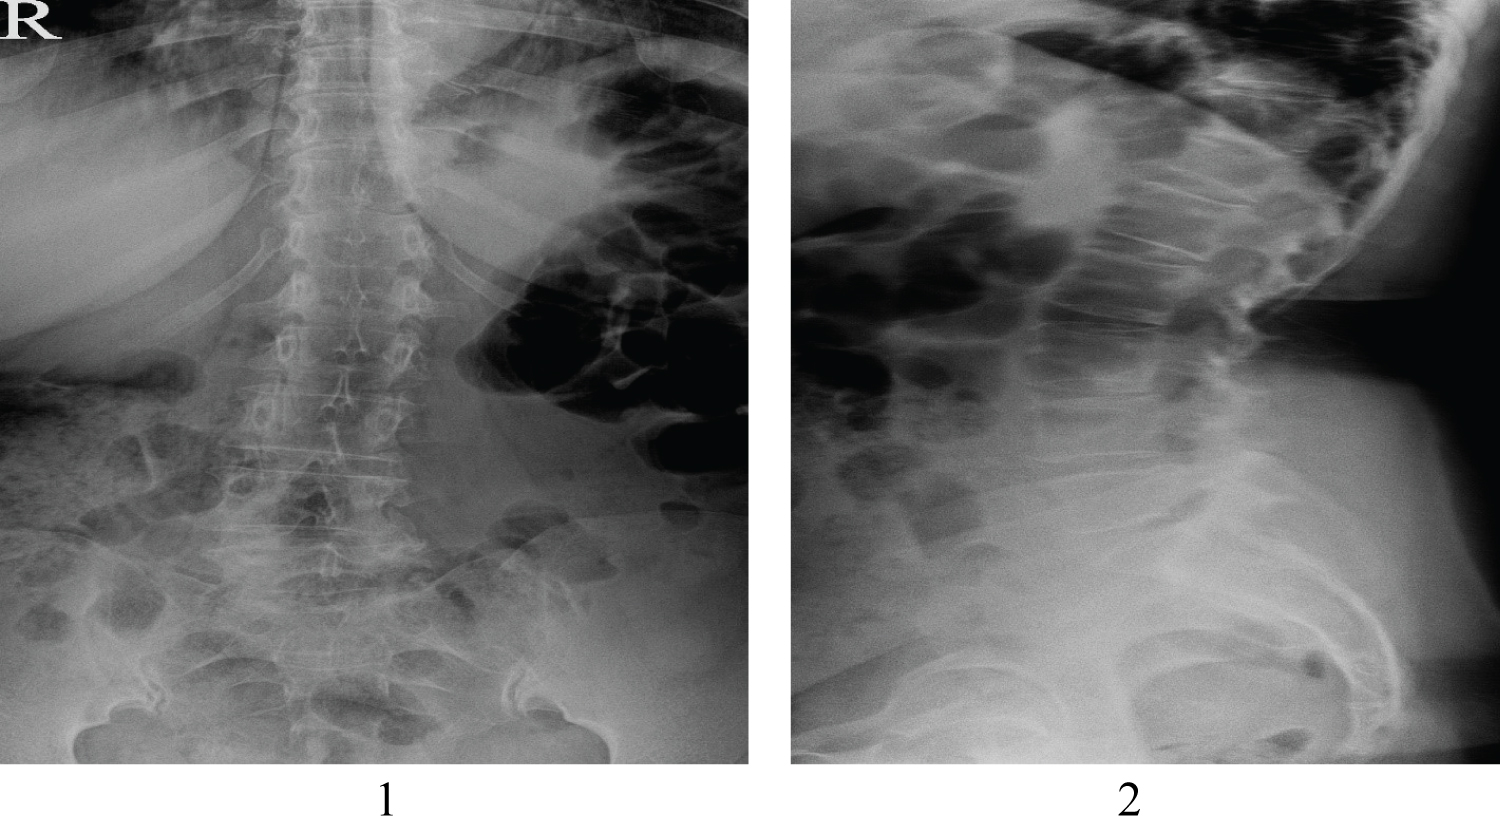

Plain X-ray showed no significant indication of chondromyxoid fibroma because of adherent structures and superposition of multiple layers (Figure 1 and Figure 2).

Figure 1 and Figure 2: Plain X-ray (anteroposterior and lateral orientations). View Figure 1&2